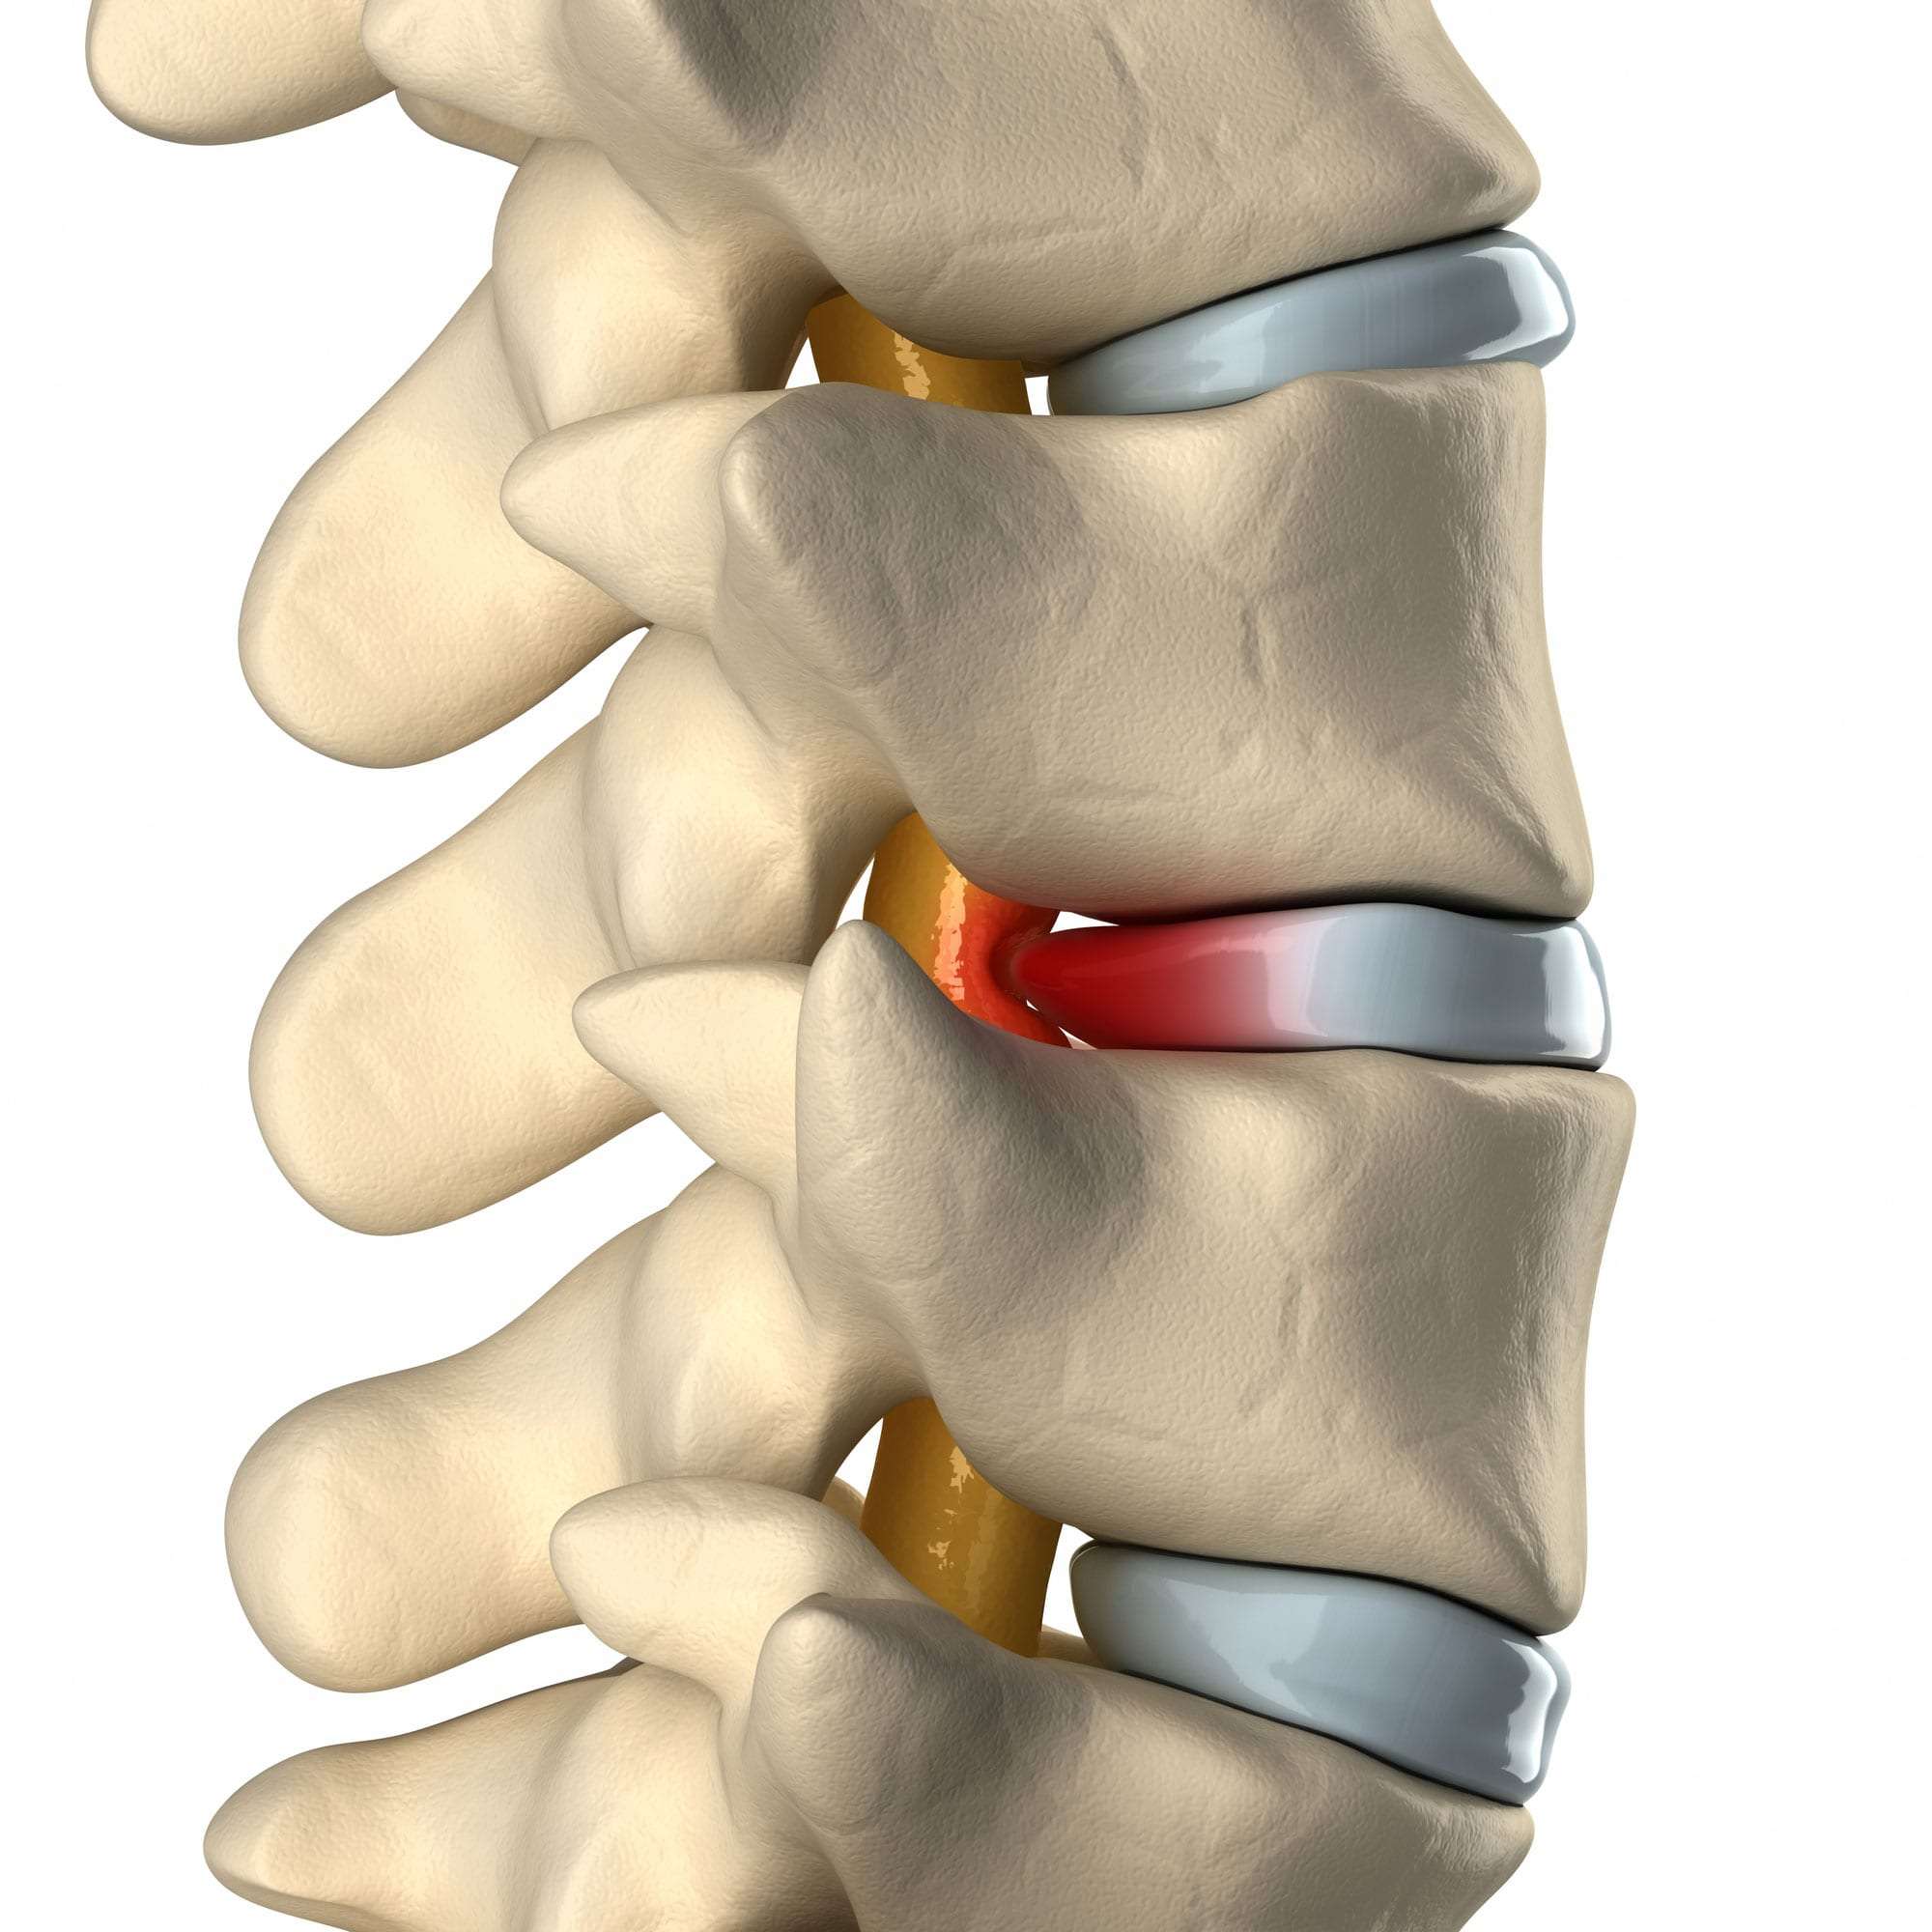

Bulging and Herniated Discs – Explained | Physical Health Care

What is the difference between a bulging disc and a herniated disc?

Herniated and Bulging Disc Treatment & Causes – Makari Wellness

Herniated, Bulging or Slipped Discs – SOS Chiro